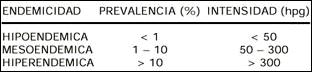

Se estima que entre 2.4 a 17 millones de personas infectadas por Fasciola hepática existen en todo el mundo, habiéndose incrementado su incidencia aparentemente desde 1980 (2,3). Típicamente ocurre en regiones temperadas, a excepción de Oceanía (7). Ejemplos de prevalencia muy reducida se dan en Francia (0.34-3.1 casos por 100 mil habitantes). Niveles intermedios se hallan en Portugal (3.2%), Egipto (7.3%) y Cajamarca (8.7%). Prevalencias altas pueden citarse en Bolivia (65-92%), Ecuador (24-53%), Egipto (2-17%), Asillo-Azángaro (Puno: 15.67-31%), valle del Mantaro (Junín: 10.7-34.2%), Jauja (27%), Huarochirí (Lima: 15%) (2,3,8-10). De acuerdo a la prevalencia en la población total obtenida por diagnóstico coprológico, pueden distinguirse tres tipos de endemicidad (2). Tabla 1.

Tabla 1. Endemicidad por fasciola hepática

a intensidad de infección es un concepto que se refiere a la expulsión de huevos por gramo de heces (hpg), que en el humano era tan baja como 1-4 hpg, no obstante en las zonas endémicas en las heces de niños (Bolivia) se han reportado entre 24-5064 hpg. Por lo demás, la magnitud del contenido de huevos son más altas en los niños (75%, 24-4440 hpg) que en los adultos (41.7%, 144-864 hpg) (2).